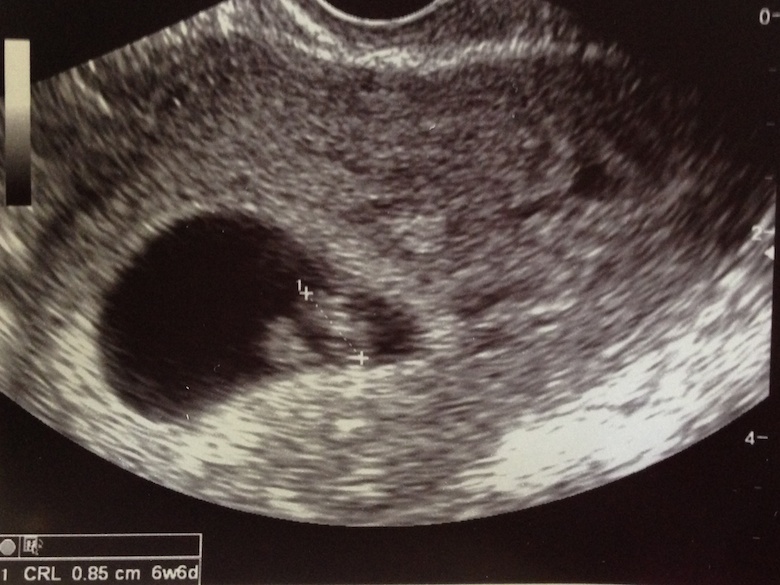

참, 예정일은 10월 6일. 이제 7주차인데, 확실히 경험이 없는 친구들은 바로, 남자냐 여자냐를 물어본다. 어이 비경험자들, 성별은 18주 후에나 알 수 있다네. 태명은 미정.